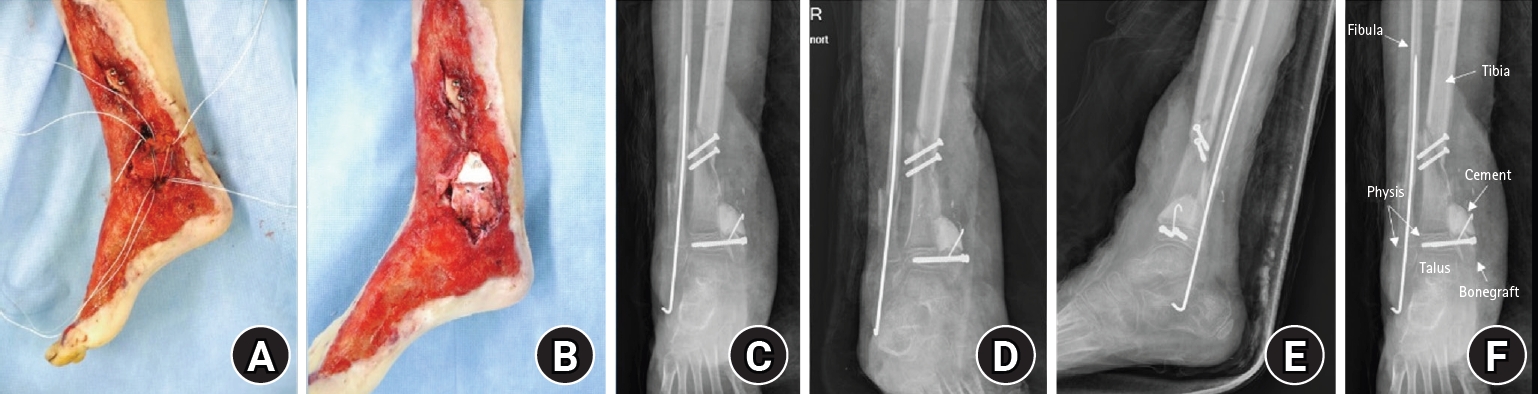

An 8-year-old girl presented after a traffic accident with a severe crush and degloving injury of the medial right ankle and foot, a distal tibiofibular fracture, and medial midfoot bone defects. After staged irrigation and debridement with temporary external fixation, definitive reconstruction was performed on August 6, 2016. The medial malleolar defect (2.5×2.0 cm) was reconstructed using a contoured autologous iliac crest bone graft secured with internal fixation, and medial stability was augmented using harvested gluteal fascia as a deltoid ligament substitute fixed with suture anchors. A bone-cement spacer was placed adjacent to the injured physis to mitigate physeal bridging, and the extensive soft-tissue defect was covered with a free anterolateral thigh flap and skin graft. During follow-up, progressive varus deformity and contracture were managed with corrective osteotomy and plating, Achilles tendon lengthening, Z-plasty, and Ilizarov fixation. At the final follow-up (March 6, 2025), the limb-length discrepancy was 5 mm, active ankle dorsiflexion was 0° (passive dorsiflexion 5°), and the patient was pain-free with full participation in daily activities, including hiking and dancing. This case emphasizes the value of an integrated staged strategy that combines bony reconstruction, medial stabilization, physeal management, and durable soft-tissue coverage during skeletal growth.